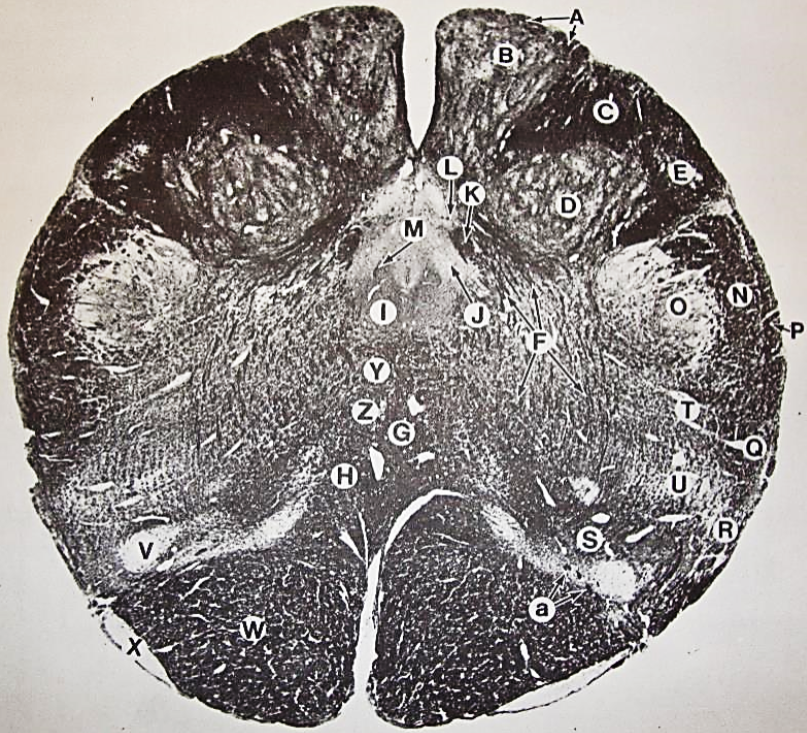

A

posterior median sulcus

B

posterior intermediate sulcus

C

anterior median fissure

D

gracile fasciculus

E

Gracile nucleus

F

fasciculus cuneatus

G

spinal trigeminal tract

H+I collectively

spinal trigeminal nucleus

J

Accessory nucleus

K

pyramidal decussation

L

lateral corticospinal tract

M

rubrospinal tract

N

posterior spinocerebellar tract

O

anterior spinocerebellar tract

P

lateral spinothalamic tract

Q

anterior spinothalamic tract

R

lateral vestibulospinal tract

S

medial longitudinal fasciculus

T

tectospinal tract

U

central canal